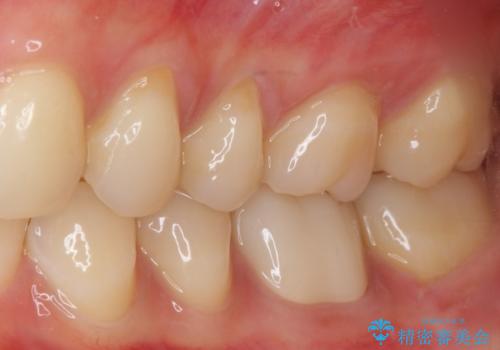

初回の治療後には歯肉に認められた排膿の出口などの症状は消えていました。

補綴後6ヶ月経過しレントゲンを撮影したところ、遠心の歯根付近の病変が消失していることが確認できました。